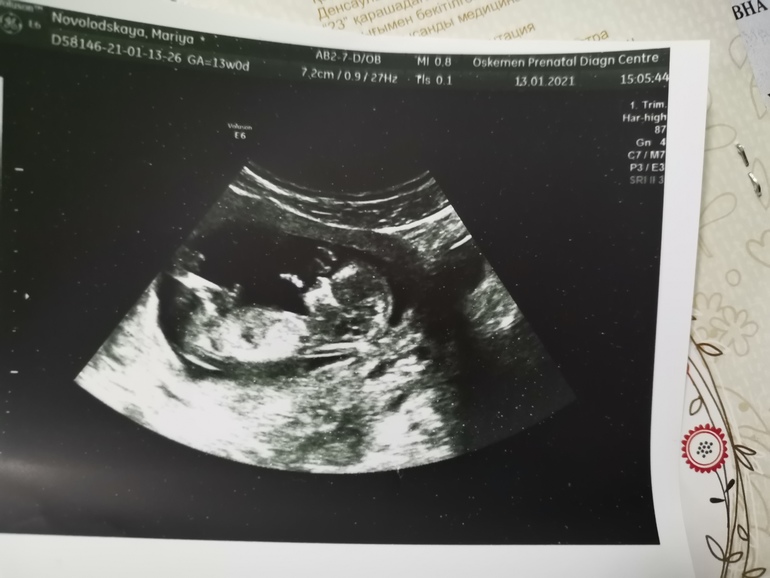

Мария в Благополучная беременность 5 лет Девочки погадаем пол малыша? Пол малыша Посмотрите еще 20 записей на эту тему Отменить Ответить Anya пацан 13.01.2021 Ответить Мария Дорогие спасибо за комментарии и предположения узист сказала что 95%мальчик 13.01.2021 Ответить Лея Владимировна Не видно ничего ((( 13.01.2021 Ответить НЮША (ник в ИГ Visla79) Похоже мальчик 13.01.2021 Ответить Мария Андреева Мальчик 13.01.2021 Ответить Леночка Тут же не видно))) 13.01.2021 Ответить Maria Мне кажется, что мальчик :) 13.01.2021 Ответить Анюта Мальчик 13.01.2021 Ответить YanaM Тут не видно 13.01.2021 Ответить Определение пола по крови.Куда пойти в Москве? Не могу решить) Чаты Беременных Выберите чат: Январята-2026 Февралята-2026 Мартята-2026 Апрелята-2026 Майчата-2026 Июнята-2026 Июлята-2026 Августята-2026